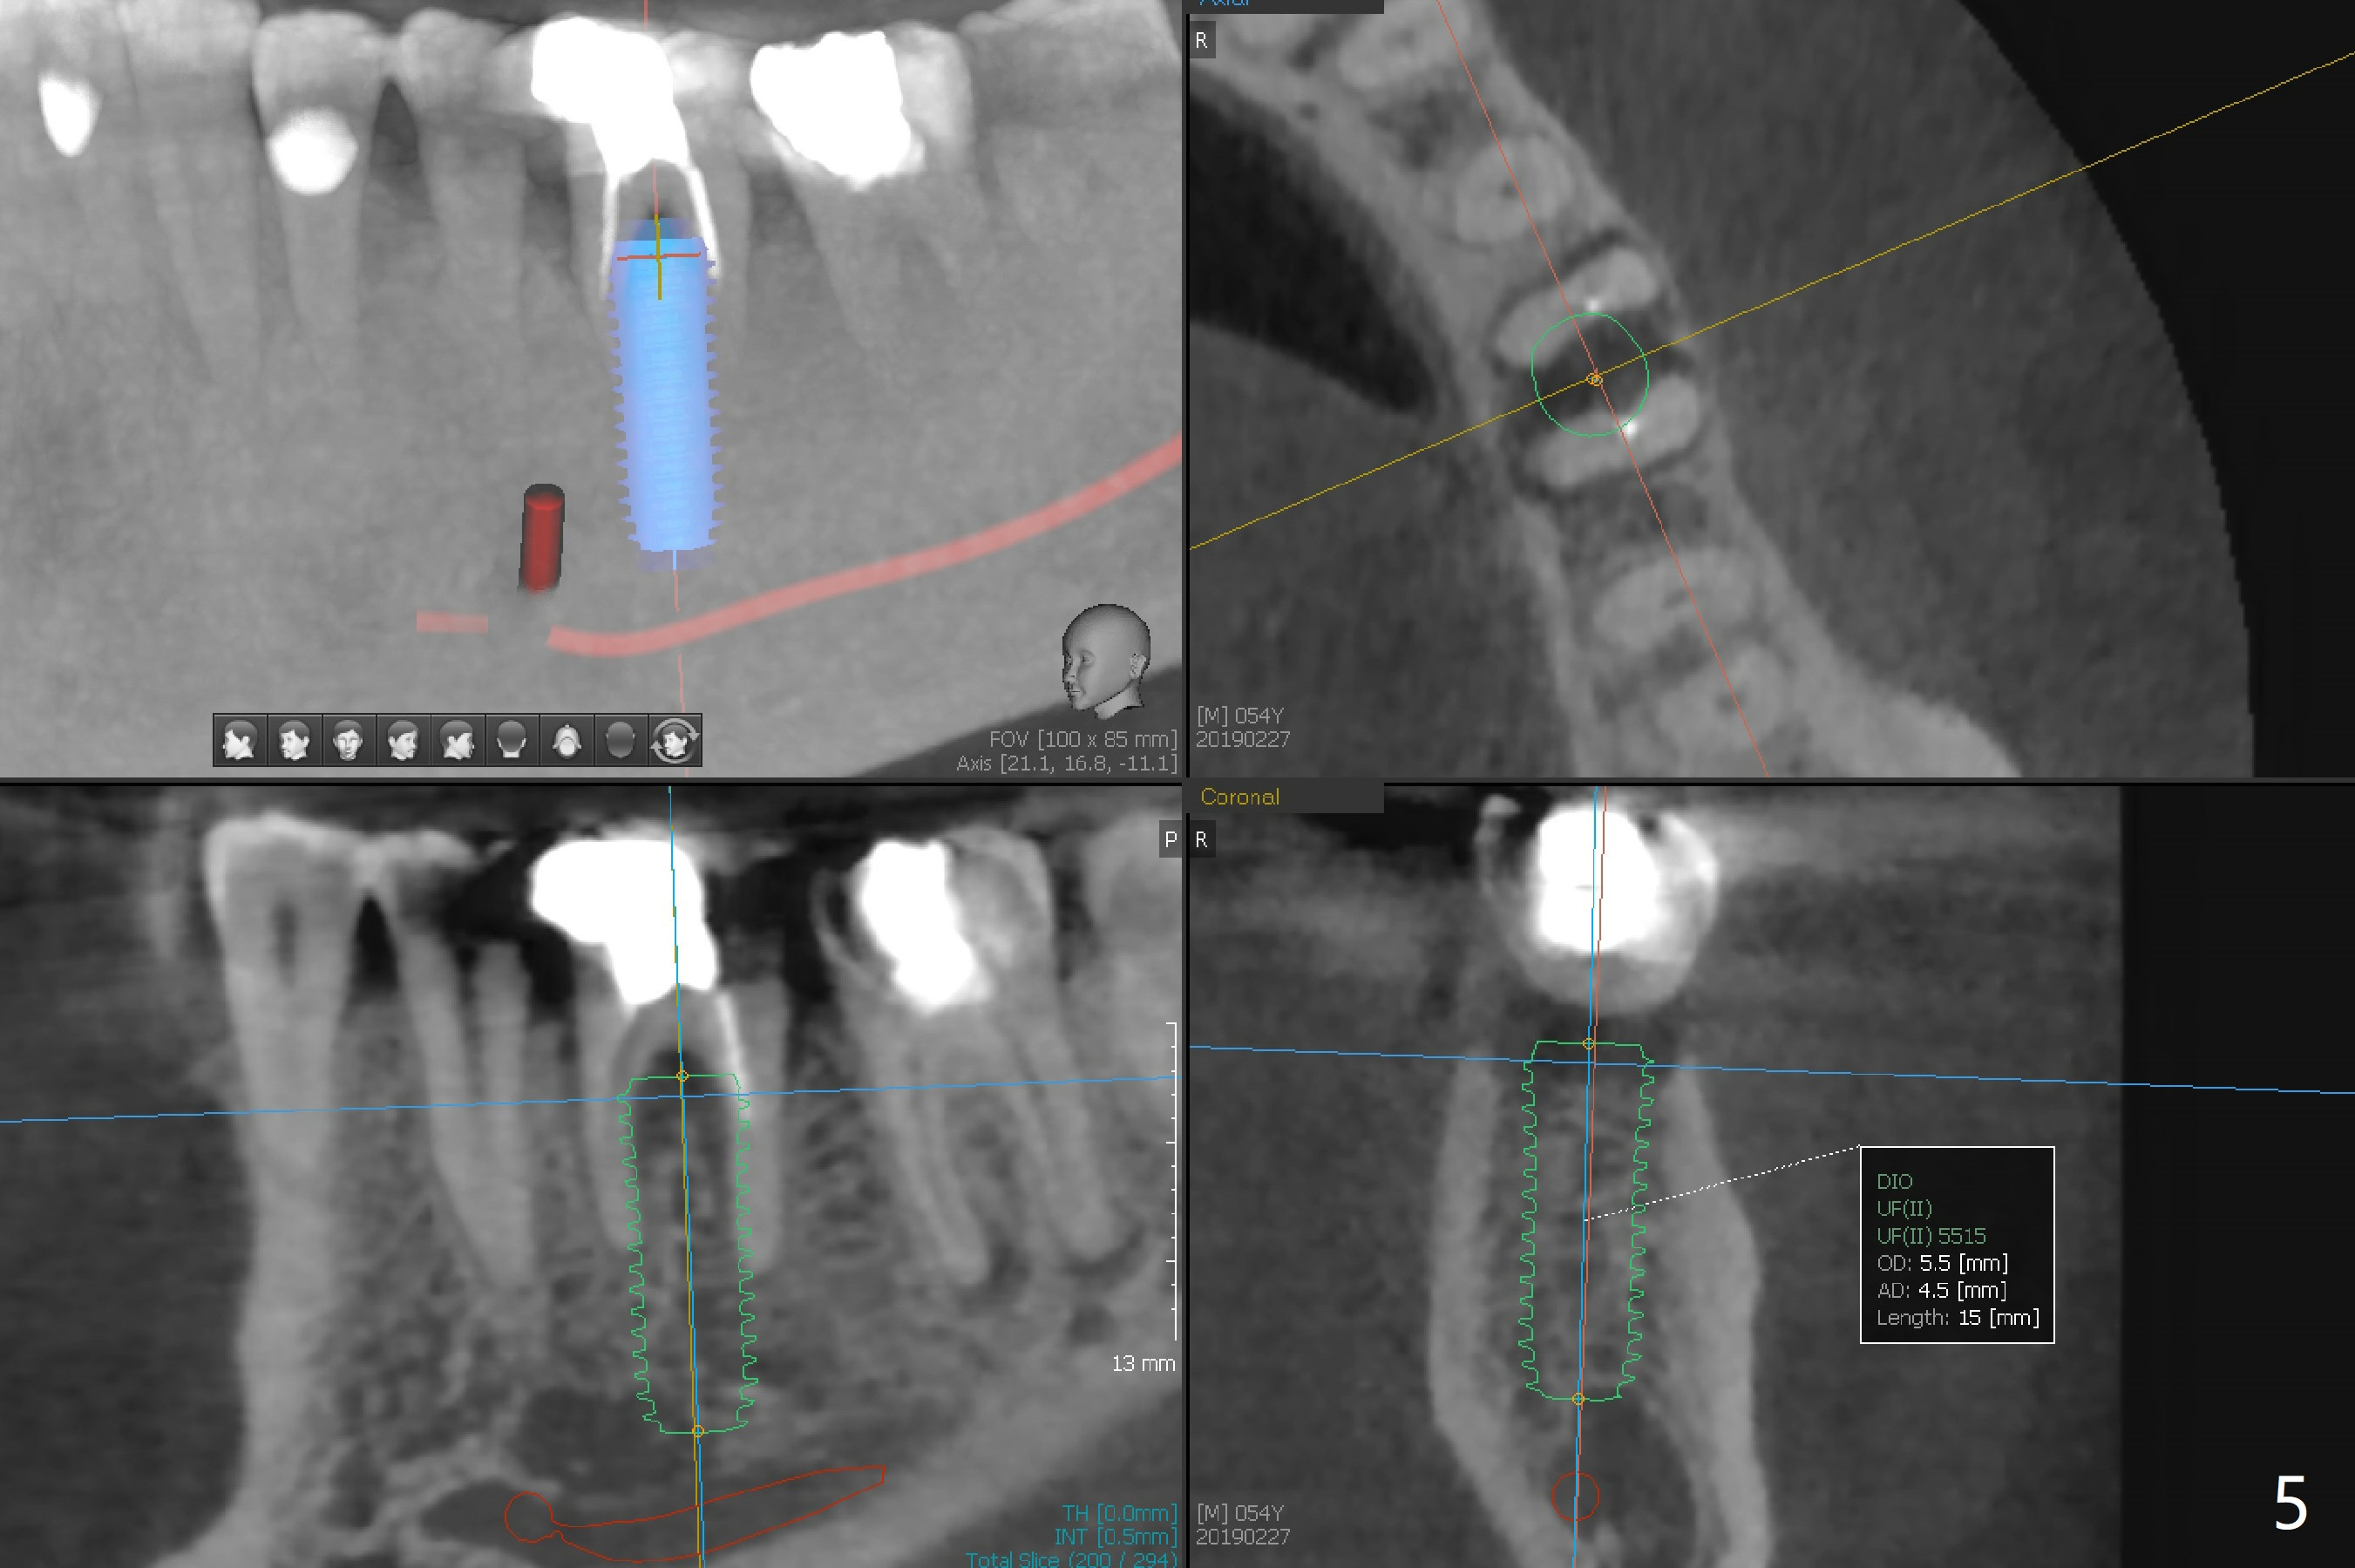

A 54-year-old man has several restoration with sign of bruxism (Fig.1). The tooth #19 has mesiodistal crack with furca radiolucency (Fig.2 *). To prevent abutment screw loosening associated with heavy mastication, a 6x17 mm tissue-level implant will be placed free hand due to the patient's tight schedule (blue, Fig.3,4,5). Pink: abutment; green: restoration which will be seated partially in the implant to reduce abutment loosening. To reduce possible neuropathy and have freedom to place implant deep, the implant length will be shorter, 14 mm, if the bone is dense. Take photos to show the crack line and buccal swelling. The patient returns for implant 4 months post extraction without bone graft in his home country with bone loss (Fig.6). In the presence of the accessory canal (Fig.7 *), a 5x10 mm implant is safe to be placed.